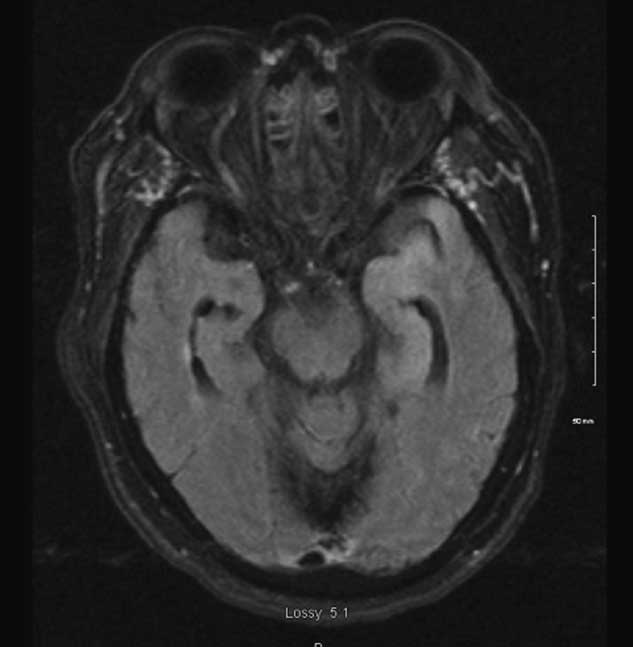

Subsequent MRI demonstrated cortical expansion and abnormal signal intensity of the left anterior temporal lobe and hippocampus (Figure 1). CSF analysis demonstrated 75×106/L neutrophils, 17×106/L lymphocytes, and 8×106/L monocytes; 16,550×106/L red cells; 6.0 mmol/L glucose; and 1.24 g/L protein. Bacterial gram stain and culture of CSF were negative. PCR of CSF was positive for HSV DNA. On the basis of clinical history and these findings she was diagnosed with HSV encephalitis and continued on IV acyclovir 10 mg/kg/dose q8 hours. All antibiotics were discontinued. Other infectious work up including HIV, Hepatitis B&C, and bacterial cultures were negative.

Figure 1 MRI demonstrating mild cortical expansion and increased T2/FLAIR signal intensity of the left anterior temporal lobe and hippocampus.